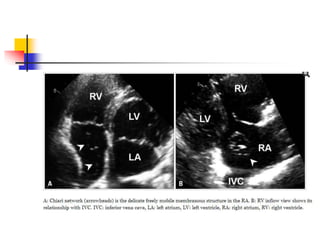

Chiari network

 Chiari network is a thin, web-like fenestrated

membrane that attaches along the ridge connecting

vena cavae and interatrial septum.

 It is found in 2-3% of normal heart at autopsy.

 In echo, Chiari network appears as free floating

curvilinear structure that waves with blood flow in RA.

 Chiari network is thought to a variant of Eustachian

valve.

 A part of Chiari network arises from the orifice of IVC

like Eustachian valve, but Chiari network is much

more mobile and thinner.

 Chiari network may be confused for tricuspid

vegetation, flail tricuspid valve, free RA thrombus,

and pedunculated tumors.

 Careful tracing to identify its attachment to the orifice

of IVC makes a differential diagnosis.

 Chiari network has little clinical significance, but it

might cause trouble during percutaneous procedures.

 cases of entrapment of right-heart catheters, or

entanglement and herniation into the LA by atrial

septal defect occluding device have been reported.